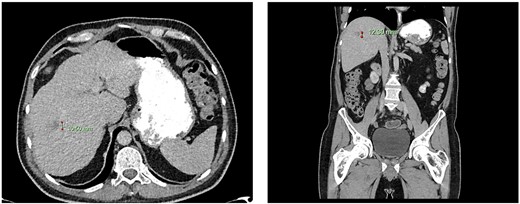

Computed tomography dated 25 September 2012 of the abdomen and pelvis measuring 18.65 mm (anterior–posterior) lesion at liver segment 5/6 in axial (left) and coronal (right) view.

Computed tomography dated 15 January 2013 of the abdomen and pelvis measuring 10.50 mm (anterior–posterior) lesion at liver segment 5/6 in axial (left) and coronal (right) view.

Subsequent surveillance imaging including magnetic resonance imaging and CT scans demonstrated gradual reduction and eventual complete resolution of the liver metastases (refer to Figs 1–4). Furthermore, routine colonoscopy and a positron emission tomography (PET) scan revealed no evidence of locoregional cancer recurrence nor distant metastatic disease present; essentially rendering the patient cured from an initial diagnosis of metastatic rectal cancer. It has been at least a decade since his initial diagnosis and the patient remains in remission.

Computed tomography dated 12 March 2013 of the abdomen and pelvis measuring 8.70 mm (anterior–posterior) lesion at liver segment 5/6 in axial (left) and coronal (right) view.